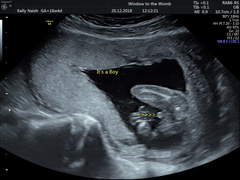

Booked in for a last minute gender scan this morning!!! I'm 18 weeks today and I was just bursting with anticipation!!! Baby was so perfect in the scan!!! They got great images and confirmed the sex!!

We are having a GIRL and I am so so so excited!! This was what i had hoped for 💖🙏👌

kisses4u · 15/12/2018 20:32

we got 4D images which I didn't realise we were getting! She looks just like her big brother 😍

Congratulations @kisses4u! Another little girl in the group 💕How exciting! Lovely pictures too!

So i did mamage to get scan yesterday partly cos i was worried again and felt stomach bit smaller... but all was fab heard heartbeat for the firat time and to my suprise found out that im DEFINITELY having a boy 😂 now the birth is worrying cos hes starting off just like his dad and hes 6'2 and has size 13 feet 😣

Congrats @Swisbest2 &@dreaminofholidays! Aw a little boy! Yup no denying with those pics! Understand how you guys feel - it was Christmas last year that I had my first miscarriage & am feeling like I'm needing lots of reassurance more than usual with kicks and things- doesn't help being so busy that it's harder to notice them 🙁 going to see how today goes but may ring midwife if I don't feel any more movements throughout the day I think...